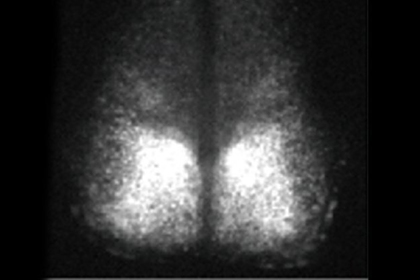

В качестве живого образца использовался фрагмент супрахиазматического ядра, который отвечает за поддержание циркадных ритмов. Мыши, у которых изъяли мозговые клетки, были генетически модифицированы таким образом, что биоритмы в мозге оказались связаны с выработкой флуоресцентного белка. Как отмечают ученые, флуоресцирование происходило в течение 25 дней. Контрольный образец, находящийся в чашке с питательной средой, начал терять активность уже через 10 часов.